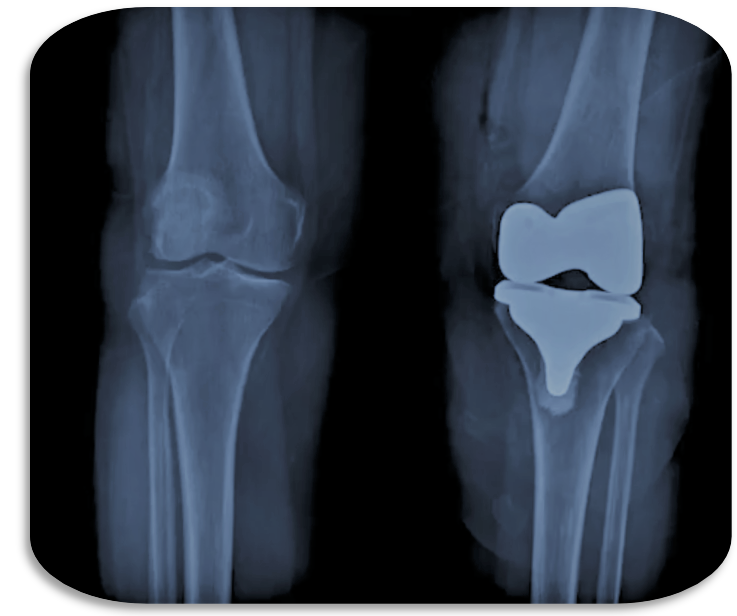

案例2 膝关节置换